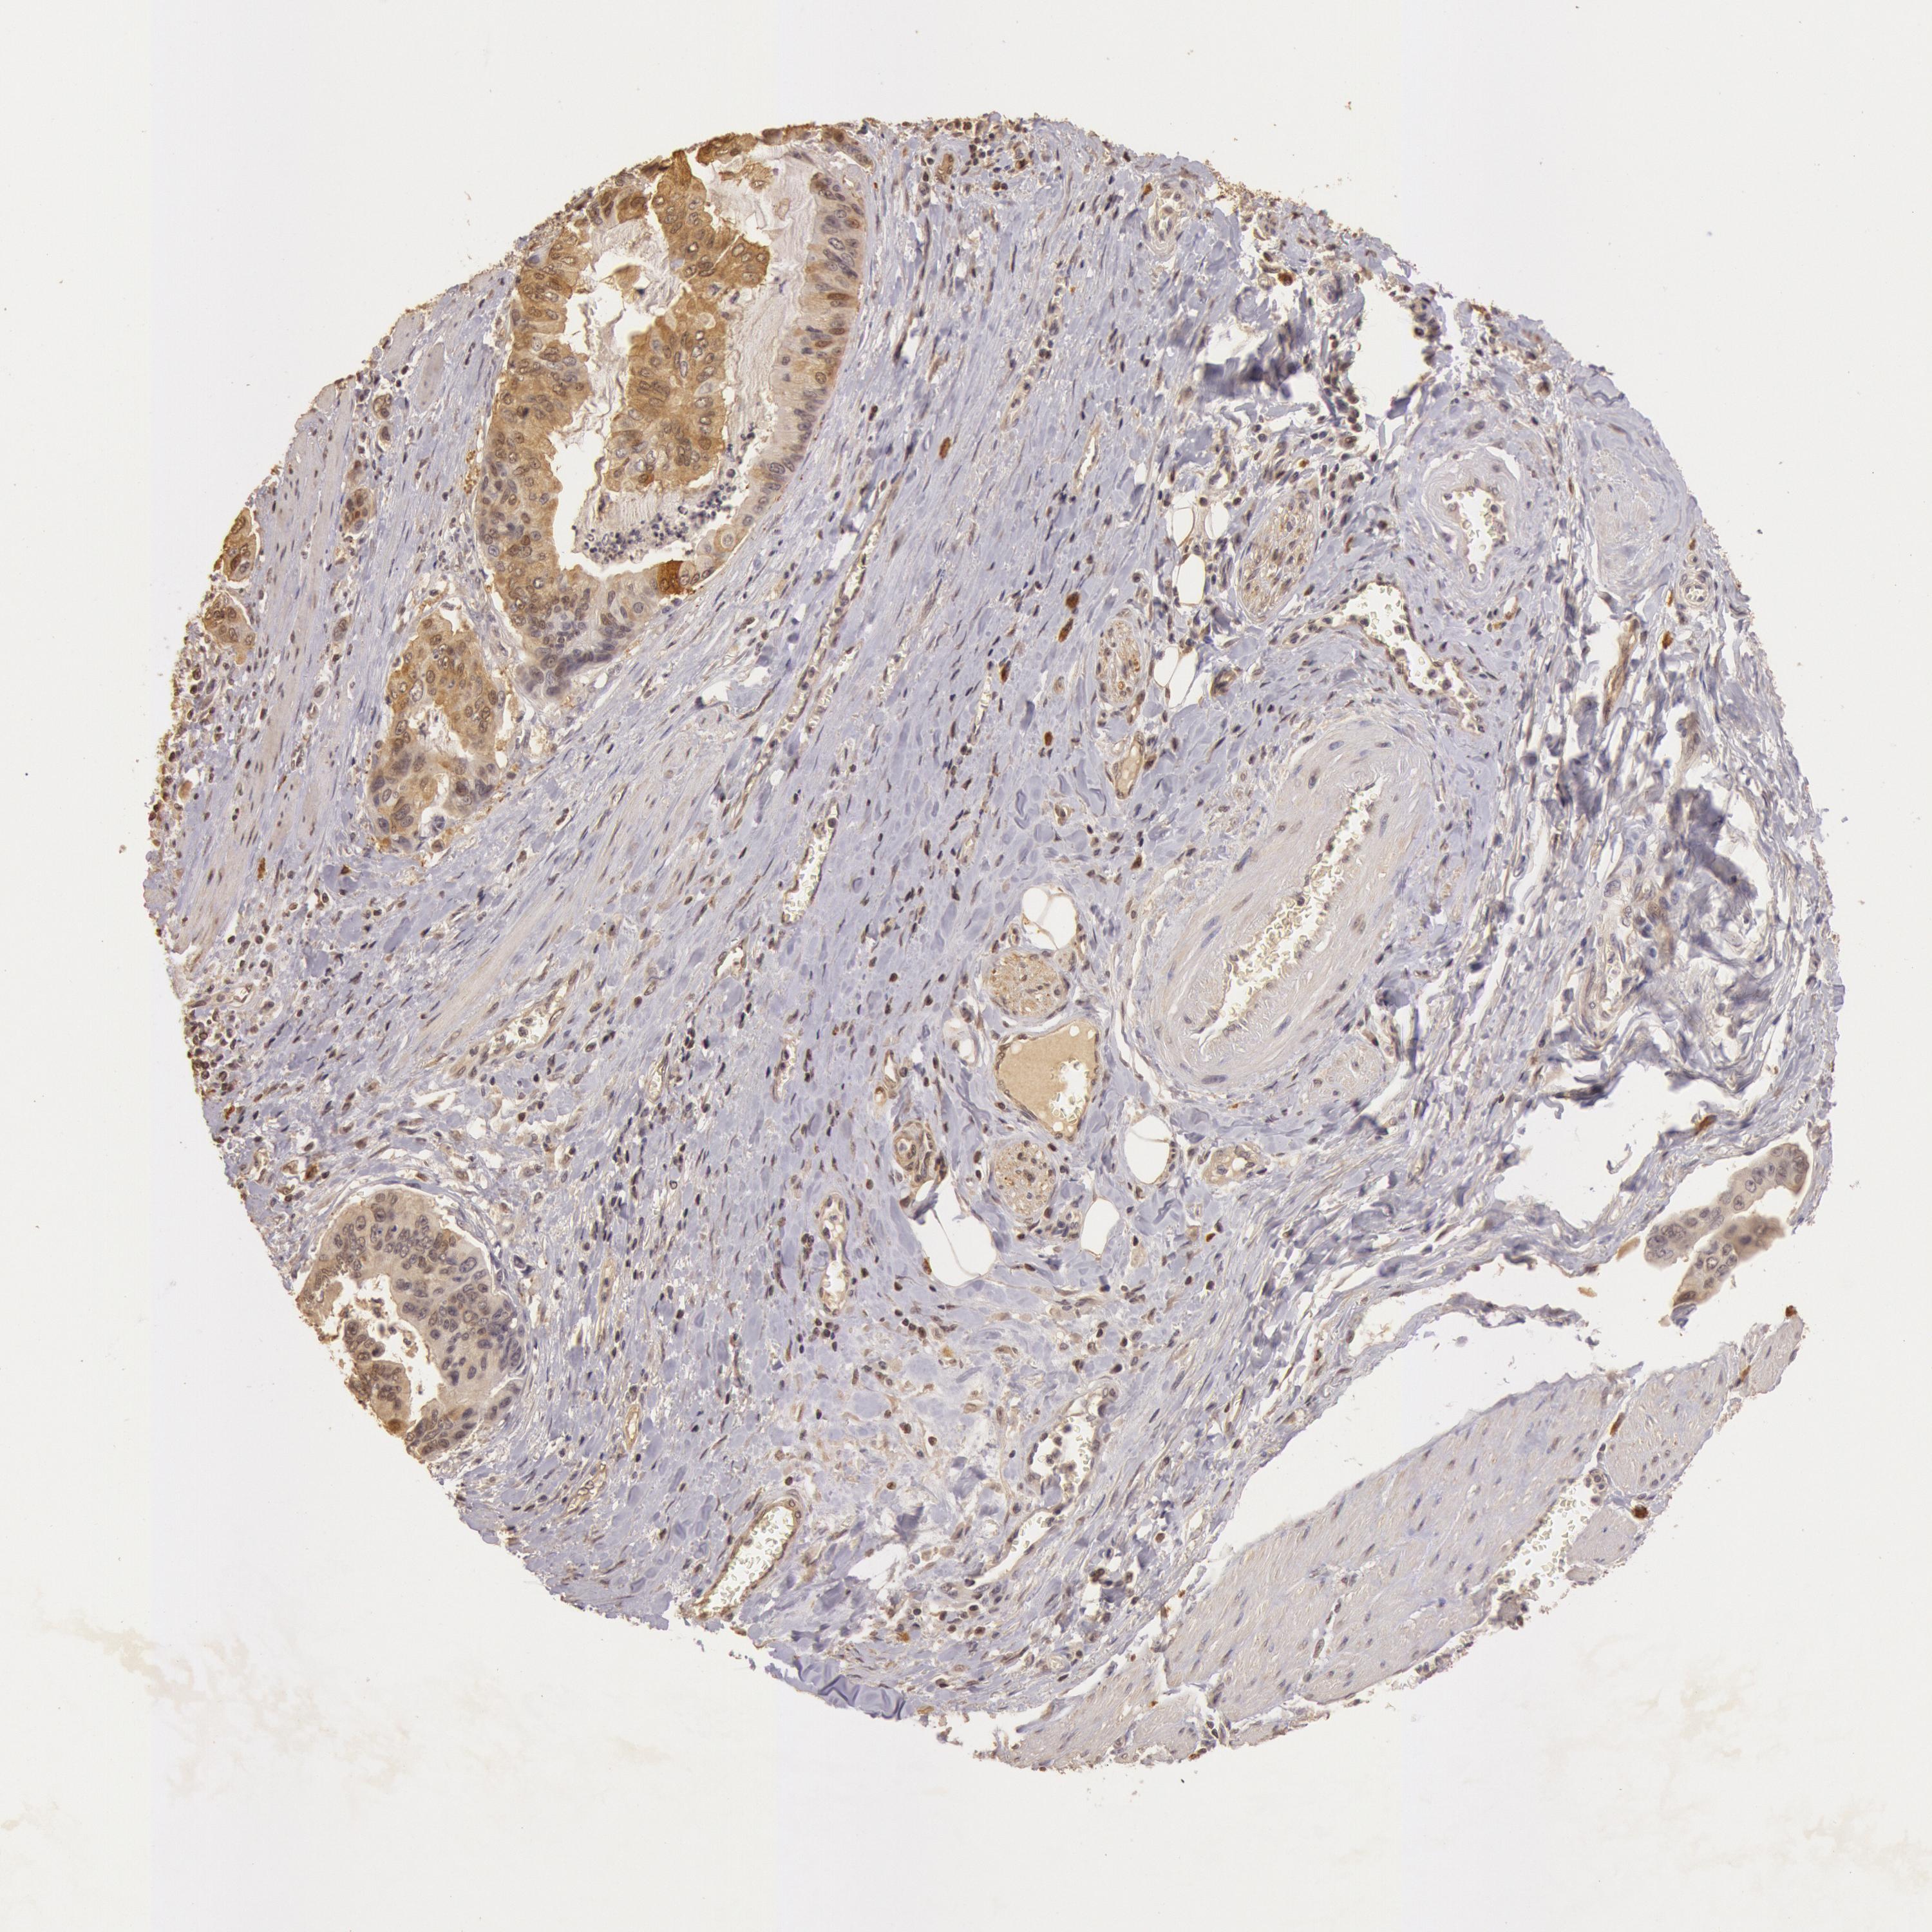

STOMACH CANCER - Protein expressioni

A mouse-over function shows sample information and annotation data. Click on an image to view it in a full screen mode. Samples can be filtered based on level of antibody staining by selecting one or several of the following categories: high, medium, low and not detected. The assay and annotation is described here.

Antibody stainingi

Antibody staining in the annotated cell types in the current human tissue is reported as not detected, low, medium, or high, based on conventional immunohistochemistry profiling in selected tissues. This score is based on the combination of the staining intensity and fraction of stained cells.

Each image is clickable and will lead to virtual microscopy that enables deeper exploration of all samples and also displays staining intensity scores, fraction scores and subcellular localization as well as patient and tissue information for each sample.

Antibody HPA001401

Antibody CAB008670

Staining

High

Medium

Low

Not detected

Intensity

Strong

Moderate

Weak

Negative

Quantity

>75%

75%-25%

<25%

None

Location

Nuclear

Cytoplasmic/membranous

Cytoplasmic/membranous,nuclear

Adenocarcinoma, NOS